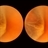

- small elevated cystic area, peripheral retina, meridional fold, ora serrata

- This is the eye of a 53-year-old woman with a small elevated cystic area of the peripheral retina at the posterior end of a meridional fold.